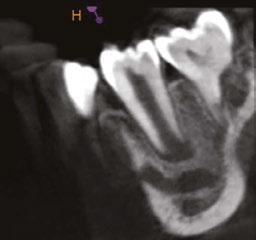

Figure 3 (left): Preoperative CBCT scan of tooth No. 20 showing evidence of a wide open apex. Figure 4 (right): Bleeding noted in the canal immediately after removing the GentleWave platform

A 10-year-old female patient with a history of swelling and pain associated with tooth No. 20 was referred to our office. The patient exhibited severe dental anxiety. Upon clinical evaluation, a dens evaginatus was noted on the occlusal surface of the tooth (Figure 1). The tooth was sensitive to percussion, palpation, and bite stick while cold testing yielded no response. A periapical radiograph and CBCT scan (Carestream 9600) revealed a wide open apex and evidence of apical periodontitis, leading to the

diagnosis of a necrotic pulp and symptomatic apical periodontitis of tooth No. 20 (Figures 2 and 3).

Figure 5 (left): Collagen tape was placed directly over the blood clot. Figure 6 (center left): Bioceramic putty was placed directly over the collagen tape. Figure 7 (center right): Periapical radiograph showing the placement of the bioceramic putty in the canal. Figure 8 (right): Restored access Figure 9 (left): Immediate postoperative periapical radiograph of tooth No. 20. Figure 10 (right): 6-month recall CBCT scan showing no evidence of apical periodontitis and calcific